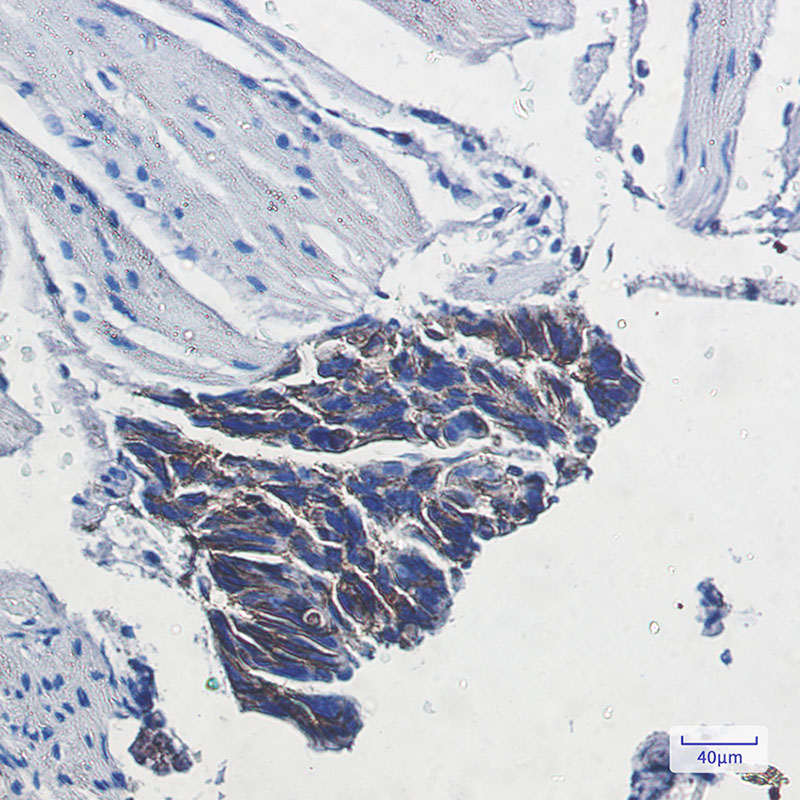

Product Image

- Immunohistochemistry analysis of paraffin-embedded Human colon cancer using ATP1B1 antibody. High-pressure and temperature Sodium Citrate pH 6.0 was used for antigen retrieval.